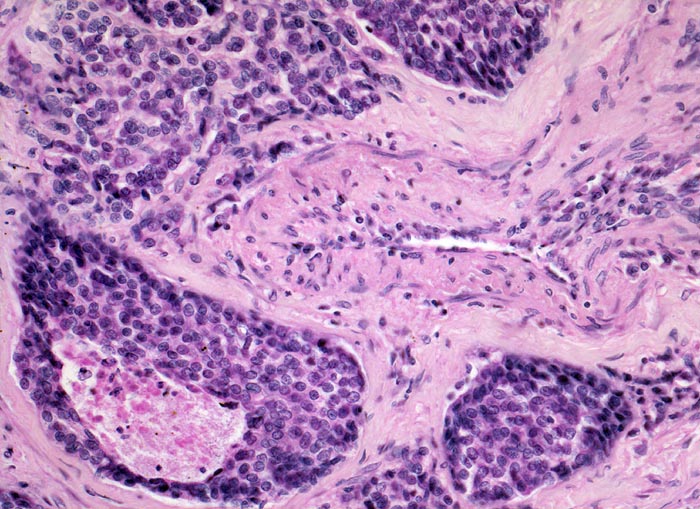

• Das Karzinom ist aufgebaut aus tubulären und kribriformen Drüsen.

• In den sternförmigen Ausläufern finden sich erweiterte Endothelausgekleidete Lymphgefässe in der Nachbarschaft von Blutgefässen.

• Die erweiterten Lymphgefässe enthalten solide Tumorzellaggregate.

• Vermehrte Alveolarmakrophagen in den peritumoralen Alveolen mit phagozytiertem Anthrakose- und Hämosiderinpigment (Rauchermakrophagen).